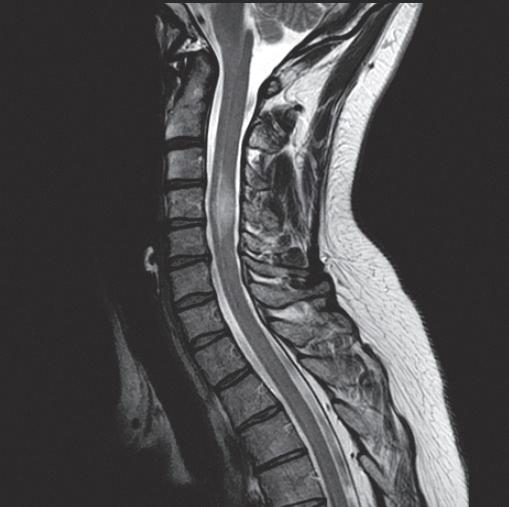

BAYCARE CLINIC NEUROLOGICAL SURGEONS

The specialists at BayCare Clinic Neurological Surgeons work collaboratively to offer comprehensive care for conditions affecting the brain, spine and nerves.

We are the longest-practicing neurological surgery team in the region, with a combined 120 years of experience.

In addition, we were the first neurosurgery team in the region to offer minimally invasive spinal fusions and artificial disc replacements.

The providers at BayCare Clinic Neurological Surgeons treat these and many other conditions:

Back pain

Neck pain

Trauma, stroke or aneurysm

Disc herniations, spinal stenosis and spinal instability

Spinal injuries and fractures

Patients seeing BayCare Clinic Neurological Surgeons for the first time must have a referral. The primary care physician, chiropractor or other medical provider will send that referral to our office. To guarantee that the patient receives the best care possible, our team fosters a collaborative relationship with the referrer. Our staff will contact each patient to schedule his or her first appointment.

Our secure, online referral portal creates a smooth, seamless pathway for you to connect with our providers on your patient’s behalf. You can securely upload medical information and send images (such as X-rays) without worry.

Patients who require specialized care for their chronic or acute back, neck, or spinal conditions can trust the expertise of our neurological surgeons.